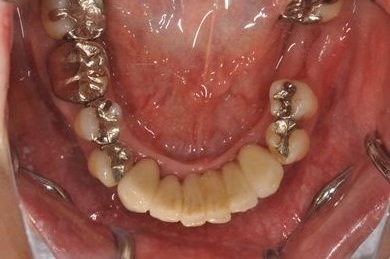

骨再生スピードインプラント治療+セラミック治療

| 性別/年齢 | 女性 / 43歳 | ||||||||||||||||||||||||||||||||

| 主訴 | 骨が薄いが、インプラント治療を希望。 | ||||||||||||||||||||||||||||||||

| 治療方針 | 抜歯と同時にインプラントを埋入し、治療期間を短縮する。ソケットリフトにて上顎洞を拳上し、インプラント治療を可能にする。 | ||||||||||||||||||||||||||||||||

| 治療内容 | インプラント9本(抜歯即日スピードインプラント、ソケットリフト、テンポラリーインプラント+仮歯)、メタルボンドセラミッククラウン18本、メタルボンドセラミックブリッジ6本(メタルボンド用土台6本)、遊離歯肉移植術 | ||||||||||||||||||||||||||||||||

| 総治療費 | 6,282,150円 | ||||||||||||||||||||||||||||||||

| 治療期間 | 1年8ヶ月 |